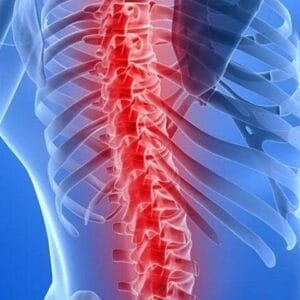

Understanding Anterior Lumbar Interbody Fusion (ALIF) in Spinal Surgery

Information for professionals Spinal.Introduction: Anterior Lumbar Interbody Fusion (ALIF) is a pivotal surgical intervention to rectify issues within the spine’s vertebrae. Essentially likened to a welding process, spinal fusion entails the fusion of problematic or unstable vertebrae, fostering the formation of a cohesive, singular bone structure. Purpose of Spinal Fusion: The primary objective